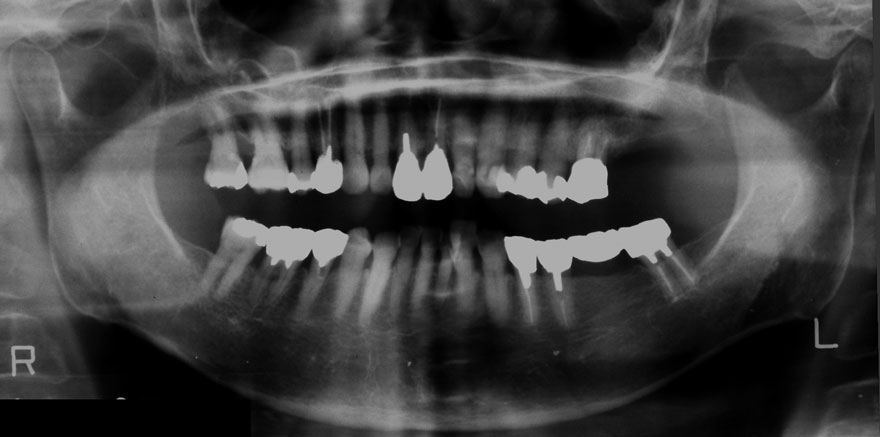

初診時 60歳 男性

29年後 89歳